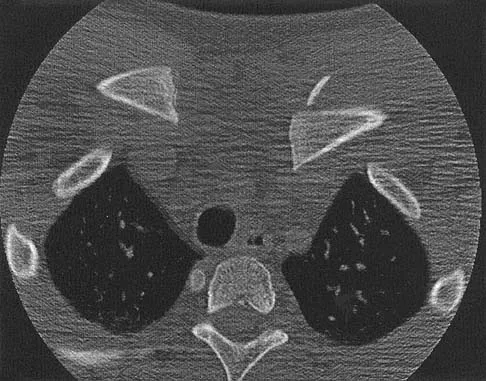

Question 60

A 13-year-old boy has a mild deformity of the left sternoclavicular joint after being involved in a rollover accident while riding an all-terrain vehicle. Examination in the emergency department reveals that he is hemodynamically stable, and his neurovascular examination is normal. The CT scan shown in Figure 22 was obtained because radiographs were inconclusive. Management should consist of

Explanation